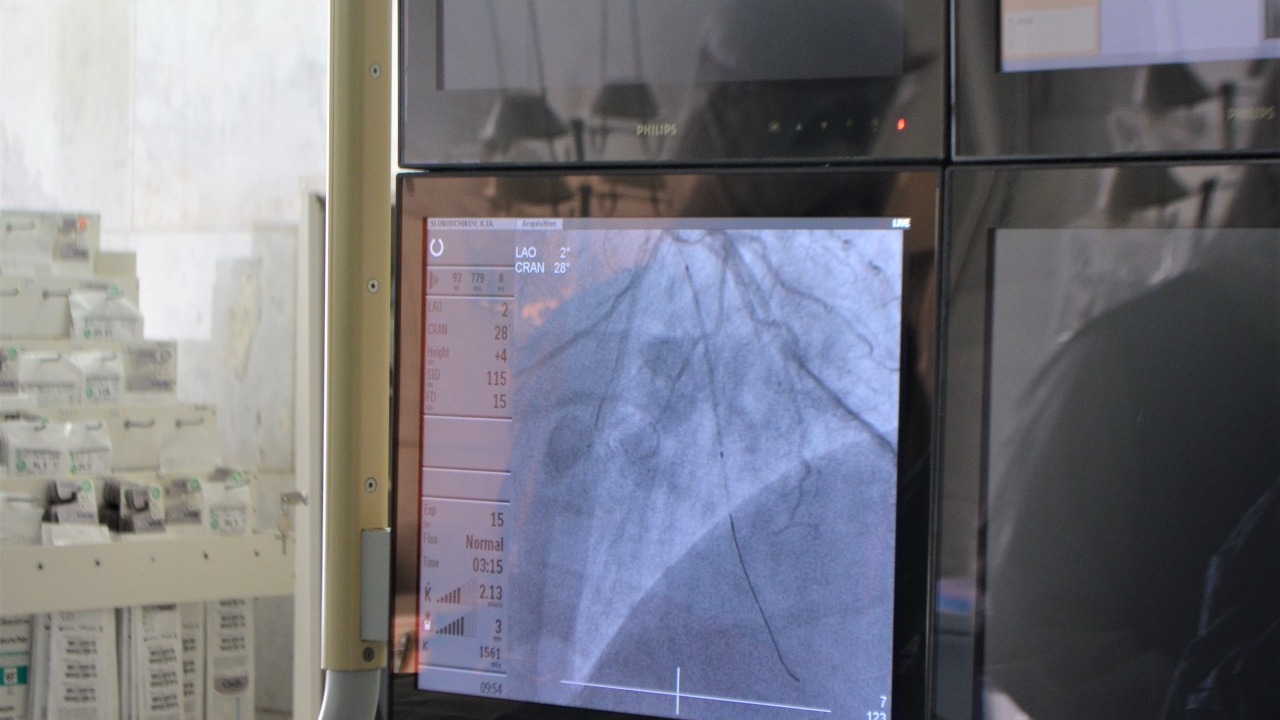

«В республике есть возможности по проведению внутреннего обследования сосуда с помощью специальных датчиков для определения бляшки, ее расположения, циркулярности. Это та методика, которая проводится только у нас в Башкирии. Она не частая, она эксклюзивная. Тем не менее, сегодня у нас есть все возможности для проведения такой процедуры. В год мы делаем порядка 5-6 таких исследований», - сказала Ирина Николаева.

«Четвертый месяц мы работаем в сложных условиях, но ни на один день кардиоцентр не останавливал прием и выписку больных сердечно-сосудистого профиля. Объемы в какой-то период времени уменьшились, но сейчас мы догоняем показатели, так как научились работать в сложных условиях. Работать непросто: наши доктора полностью одеты в защитные костюмы, плюс надевается 7-килограммовый свинцовый фартук. Мы в предоперационную заходим полностью экипированные. Это создает дополнительную нагрузку на организм и требует большей паузы между пациентами. Нужно все обработать, переодеться, немного отдохнуть. Сейчас мы научились это делать и, работать стало спокойнее и проще», - рассказала главный врач.

«Мы с помощью металлической конструкции устраняем то сужение сосудов, которое мешает жить человеку. После установки стента болезнь все равно остается. Бывает, что возникают стенозы в других местах. И здесь я всегда привожу аналогию с водопроводом. То есть, когда у нас засоряется водопровод, его нужно чистить. После того, как мы его очистили, делаем несколько вещей. Первое - не выливаем чаинки в раковину, потому что снова забьется, то есть пациенту нужно правильно питаться, внутрь себя «грязь» не пускать. Второе – в раковину мы заливаем периодически «крота», то есть человеку нужно принимать препараты. Третье – мы всегда показываем водопровод сантехникам, чтобы внезапно это не случилось, поэтому пациент должен ходить к врачам, подбирать нужные препараты. Тогда течение болезни будет благоприятным. Когда мы ставим пациенту стент, то все это объясняем, даем лекарства, меняем его образ жизни. Чаще всего, после такого подхода, пациент приходит с хорошими вестями, повторно вмешиваться не нужно. Но бывает и так, что мы все делаем, а водопровод все равно забивается. Тем не менее, вероятность того, что он забьётся, гораздо ниже у тех, кто выполняет все рекомендации», - объяснил Игорь Бузаев.